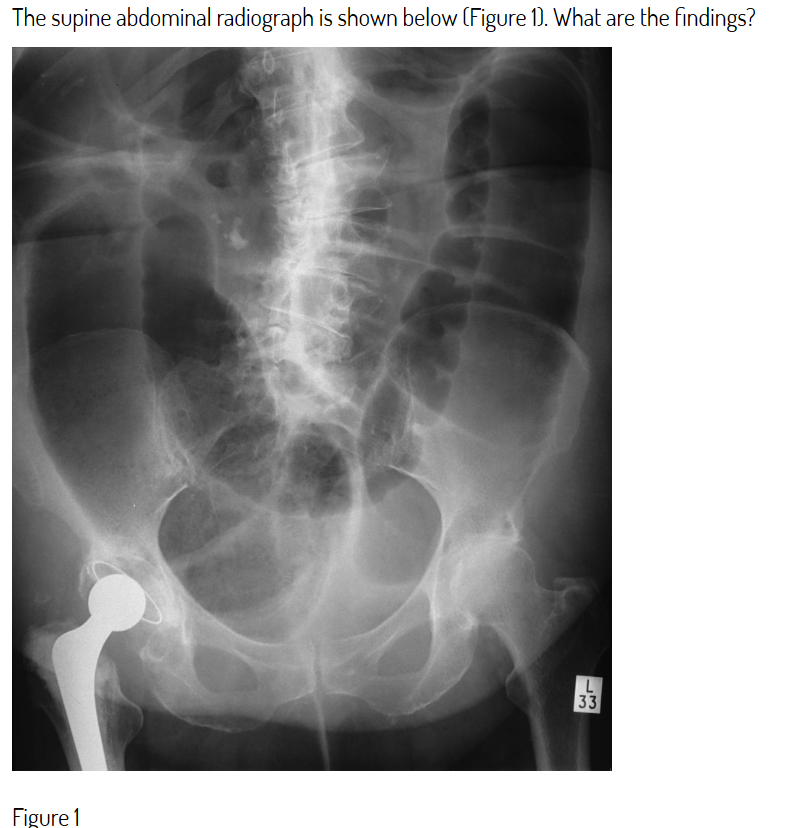

What does this AXR show?

Large bowel dilatation in keeping with obstruction extending into the pelvis

The large bowel is dilated – note haustrations to identify and peripheral distribution. There is no gas in the rectum making pseudo-obstruction unlikely. No thumb-printing is evident to suggest ischaemia. Note also right hip replacement.